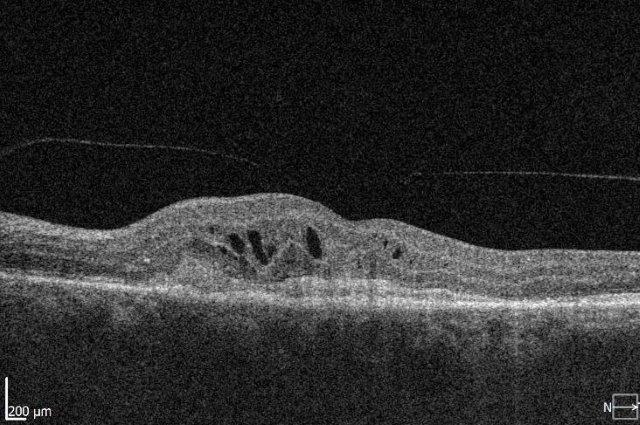

Initial clinical trials showed that anti-VEGF treatment led to stability of vision in about 90% of patients, but in the real world the results are poorer and vision can decline over time. The Fight Retinal Blindness! (FRB!) project reported five-year data of 302 patients treated for nAMD and reassuringly found stability of vision in the first affected eyes after five years of treatment (p=0.01). However, half of the patients developed second eye involvement in the study period; these eyes received fewer treatments and did lose a mean of 5.8 letters9. The main reason for patients losing vision with time is development of scarring (fibrosis) or atrophy (Fig 1). Atrophy develops in around 40% of patients within five years of nAMD treatment and is not amenable to anti-VEGF treatment10. In contrast, subretinal fibrosis is a consequence of the neovascular process and anti-VEGF treatment aims to limit or prevent development and expansion with time. Certain subtypes of nAMD, particularly predominantly classic membranes, have higher risk of fibrosis11. Newer agents targeting fibrosis should hold promise.

Fig 1. Subretinal fibrosis following delayed presentation of nAMD

Under-treatment of nAMD increases the risk of fibrosis, but many challenges exist with current agents and the frequency of injections required, impacting the patient’s ability to attend appointments and the clinic’s ability to provide timely care. Newer treatments with longer duration of effect may be helpful in improving patient adherence but there are other challenges to be considered. These include adequate funding of a health system to develop the staff and facilities to monitor and administer treatments and, ideally, more eye clinics administering injections in different geographical regions. The ability to access treatment promptly is equally important, to limit the initial damage from fibrosis or haemorrhage. Initiatives such as fast-track macular clinics or funded optometrist visits could help with this.